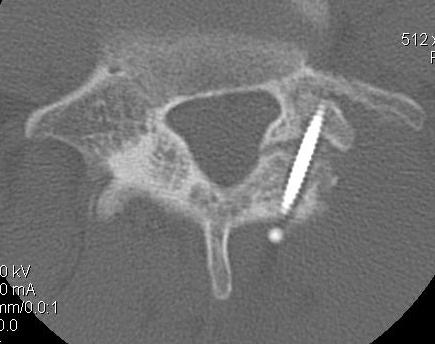

CT scan

Technique

- reverse gantry

Indication

- perform instead of obliques

- oblique x-rays have high radiation dose with little extra information compared with CT

Options ORIF

1. Screw across lytic defect

- unilateral defect

2. Pedicle screw + laminar hook

- bilateral defect

3. TBW spinous process and transverse process